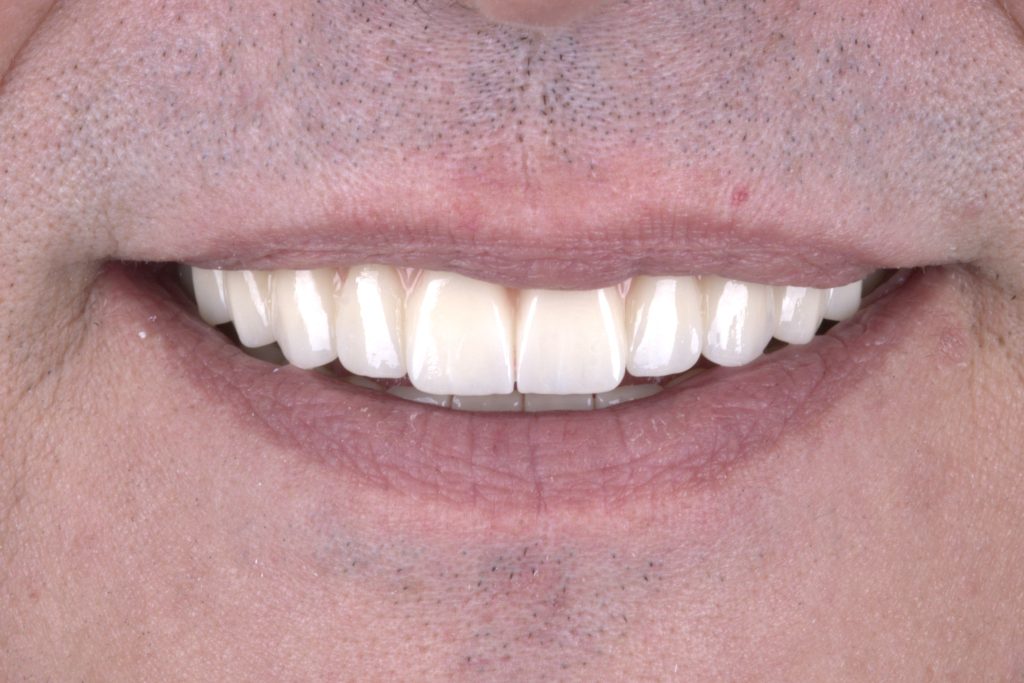

Final monolithic zirconia restoration for a double All-on-4 case study.

Finally a deserved smile Beautiful teeth

Precision-engineered occlusion, expertly crafted by our lab at White Clinic Belgrade.

Easy transition from proper provisional teeth to final ceramic restoration